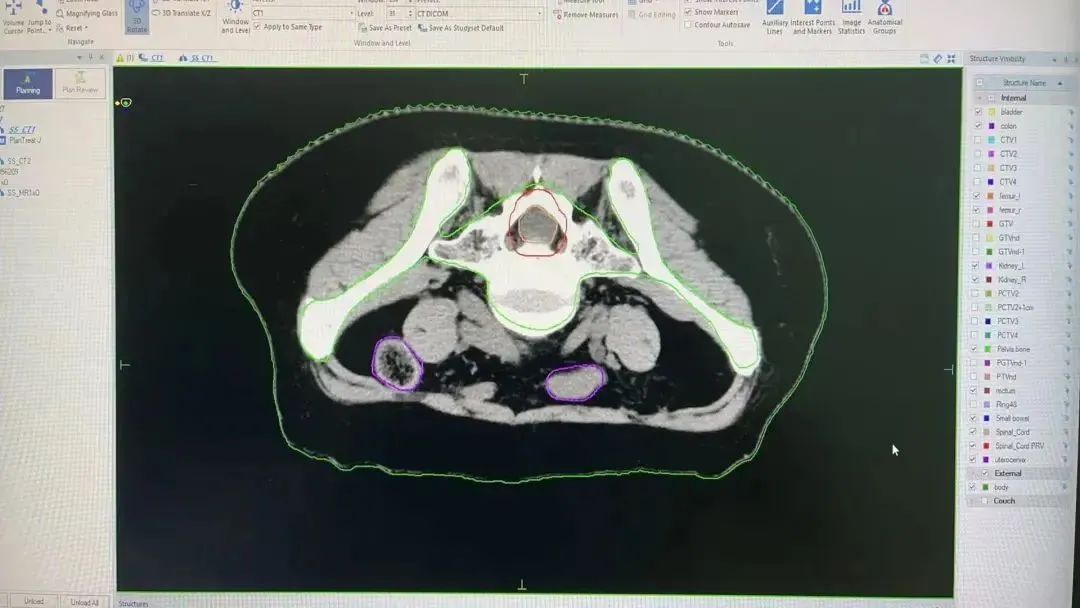

在肿瘤放疗科,直线加速器搭载AI自动勾画系统,精准定位肿瘤靶区与危及器官,有效保护正常器官,帮助医生快速、准确地确定放疗范围,显著提高放疗计划的精准性,为肿瘤患者提供更优质、更有效的治疗方案。